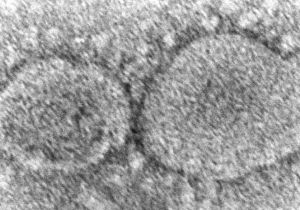

क्या चीन के वुहान लैब से लीक हुआ कोरोना वायरस? अभी भी बना रहस्य

2 Mar, 2023 08:40 PM IST | SAMIKSHASAGAR.COMनई दिल्ली व्हाइट हाउस ने कहा है कि इस बात का कोई निश्चित निष्कर्ष नहीं है...